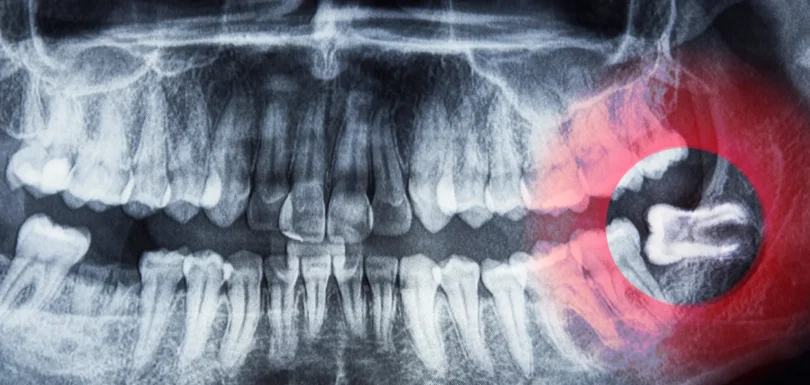

Gömülü 20’lik Diş

Gömülü 20’lik Diş: Çekmek mi Beklemek mi?

20’lik dişler (üçüncü büyük azılar), genellikle 17–25 yaş arasında sürer. Ancak çene kemiğinde yeterli boşluk olmaması veya dişin yanlış yönde çıkmaya çalışması nedeniyle bu dişler ağız içine çıkamayabilir. İşte bu durumda “gömülü 20’lik diş” problemi ortaya çıkar. Gömülü yirmilik dişler çevre dokulara baskı yapabilir, enfeksiyon ataklarına veya kist oluşumuna yol açabilir. Öte yandan, belirti vermeyen […]